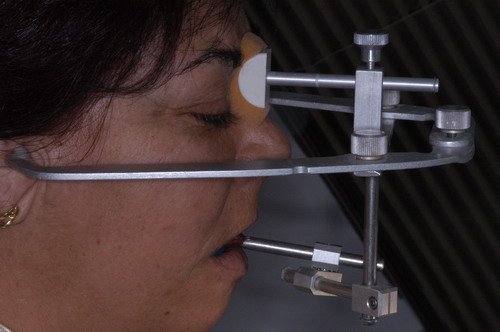

EL USO DEL ARCO GÓTICO DE GYSI , MEDIANTE UNA BÓVEDA PALATINA Y UN APOYO CENTRAL ÚNICO (BO PA YA CU) , EN LA UBICACIÓN DE LA RELACIÓN CÉNTRICA EN UN CASO DE GRAN LAXITUD TENDINOSA CAPSULAR. EL PACIENTE SE PRESENTA A CONSULTA CON UNA EDENTACIÓN PARCIAL, Y GRADO DE MOVILIDAD EXTREMO EN TODAS SUS PIEZAS REMANENTES. SE ESTUDIA EL CASO RADIOGRÁFICA Y CLÍNICAMENTE , Y EL PACIENTE RELATA ESTAR EN ESE ESTADO DESDE HACE MUCHO AÑOS. AL MANIPULAR LA MANDÍBULA EN UN INTENTO DE CONOCER EL ESTADO MUSCULAR DEL SISTEMA, SE OBSERVA UNA GRAN LABILIDAD TENDINOSA CAPSULAR QUE SE MANIFIESTA EN UNA HIPER LAXITUD EN LOS MOVIMIENTOS MANUALMENTE INDUCIDOS DE AMBOS CÓNDILOS DENTRO DE LA CAVIDAD. SE TOMAN IMPRESIONES Y SE MONTA EN UN ARTICULADOR SEMI AJUSTABLE , CORTANDO EN EL YESO LAS PIEZAS QUE SERÁN EXTIRPADAS , CONSERVANDO UNICAMENTE , AMBOS PRIMEROS PREMOLARES INFERIORES , QUE SERÁN UTILIZADOS PARA RETENER MEDIANTE RETENEDORES ELÁSTICOS LA PRÓTESIS INFERIOR , EN LA PRESUNCIÓN DE LA HIPERMOVILIDAD A QUE SERÁ SOMETIDA DADO QUE EN LA GRAN REABSORCIÓN ÓSEA , ES FRECUENTE EL ACERCAMIENTO DE TODAS LAS INSERCIONES MUSCULARES A LA PORCIÓN SUPERIOR DEL REBORDE ÓSEO , LO QUE ATENTARÁ CONTRA LA ESTABILIDAD DE DICHA PRÓTESIS PROVISIONAL. EN UNA PRIMERA SESIÓN CLÍNICO QUIRÚRGICA , SE EXODONCIA TODO EL SECTOR INCISIVO Y CANINO INFERIOR , Y AL OBSERVAR EL REMANENTE ÓSEO CANINO DE AMBOS LADOS , SE IMPLANTA EN FORMA INMEDIATA . TANSCURRIDOS DOS MESES , DONDE LA CICATRIZACIÓN ES ADECUADA , Y LA DINÁMICA MANDIBULAR ACEPTABLE , SE PROCEDE A LA ETAPA QUIRÚRGICA IMPLANTARIA MEDIANTE IMPLANTES SEMI SUMERGIDOS, CON ALGUNAS ZONAS DE REGENERCIÓN ÓSEA GUIADA FIG17 FIG18 FIG19 FIG26 DURANTE LA ETAPA DE CICATRIZACIÓN DE ESTE NUEVO ABORDAJE QUIRÚRGICO , SE ENDODONCIAN AMBOS PREMOLARES INFERIORES CONSERVADOS , LOS QUE EN UN FUTURO , CUANDO YA NO SIRVAN PARA RETENER LA PRÓTESIS REMOVIBLE PROVISORIA INFERIOR , SERÁN CORTADOS COMO RESERVA DE CAPITAL ÓSEO O BIEN COMO ELEMENTO RETENEDOR ANTE CUALQUIER TIPO DE INCIDENCIA IMPLANTARIA. ABORDAMOS LA ETAPA PRIMARIA PROTÉTICA , UNA VEZ TRANSCURRIDOS TRES MESES, MEDIANTE LA UTILIZACIÓN DE CUBETAS INDIVIDUALES , A LAS QUE REALIZAMOS UN RECORTE MUSCULAR EN BASE A STENS VERDE , COMO SI DE UNA PRÓTESIS COMPLETA SE TRATARA. DE ESE MONTAJE OBTENEMOS DOS RODETES DE METACRILATO , PERFECTAMENTE ADAPTADOS A LOS MODELOS FUNCIONALES , A LOS QUE LES OTORGAMOS LA PLANIMETRÍA DERIVADA DEL PARALELISMO CON EL PLANO DE FRANKFURT , Y UNA ALTURA (DV) QUE RESULTA DE LOS MÉTODOS MÉTRICOS DE DIMENSIÓN VERTICAL… Y QUE NOS SERVIRAN ADEMÁS DE TOMAR UNA NUEVA IMPRESIÓN FUNCIONAL MEDIANTE RECORTE MUSCULAR , PARA ADAPTAR UN DISPOSITIVO CONSISENTE EN UNA BÓVEDA PALATINA SUPERIOR , Y UN TORNILLO CENTRAL INFERIOR , LOS QUE DESPUÉS DE UN ENTRENAMIENTO ADECUADO DEL ENFERMO , NOS PERMITIRÁ REPRODUCIR EN EL BÓVEDA , EL ARCO GÓTICO DE GYSI , ENCONTRANDO DE ESTA MANERA LA OCLUSIÓN EN RELACIÓN CÉNTRICA. ACTUALMENTE ESTE MÉTODO HA SIDO RECREADO MEDIANTE LA DENOMINACIÓN DE: FIG50 FIG51 FIG52 OBTENIDO EL DIBUJO DEL ARCO GÓTICO , INSINUAMOS EN EL VÉRTICE DEL MISMO UNA PERFORACIÓN QUE FIJARÁ LA PUNTA DEL TORNILLO EN ESA POSICIÓN: RELACIÓN CÉNTICA FIG55 FIG56 FIG57 CON ESTOS PARÁMETROS SE CONSTRUYEN DOS SOBREDENTADURAS ABROCHADAS EN RÓTULAS SUPRA IMPLANTES , QUE LE OTORGAN FIJACIÓN SUFICIENTE , DANDO A LA OCLUSIÓN TODOS LOS ELEMENTOS DE UNA: OCLUSIÓN MUTUAMENTE COMPARTIDA, REFERENCIA II CON UN ESQUEMA OCLUSAL DE : FUNCIÓN DE GRUPO BILATERAL POSTERIOR DE ACCIÓN CANINA DESPUÉS DE LAS REVISIONES PERTINENTES A LA SEMANA , EL MES Y LOS SEIS MESES DE TERMINADA LA REHABILITACIÓN , SE CITA AL ENFERMO PARA UN NUEVO CONTROL AL AÑO Y MEDIO Y SE OBSERVA UNA PERFECTA SITUACIÓN TISULAR , CLINICA Y RADIOGRAFICAMENTE CONTROLADA , Y ADEMÁS LA PERMANENCIA DEL MISMO ESQUEMA OCLUSAL OTORGADO DESDE EL PRINCIPIO. SE CONTROLA RADIOGRAFICAMENTE Y SE DA EL ALTA DEFINITIVA RECOMENDANDO EL CONTROL DOS VECES AL AÑO. REFERENCIAS: I : II. : III: